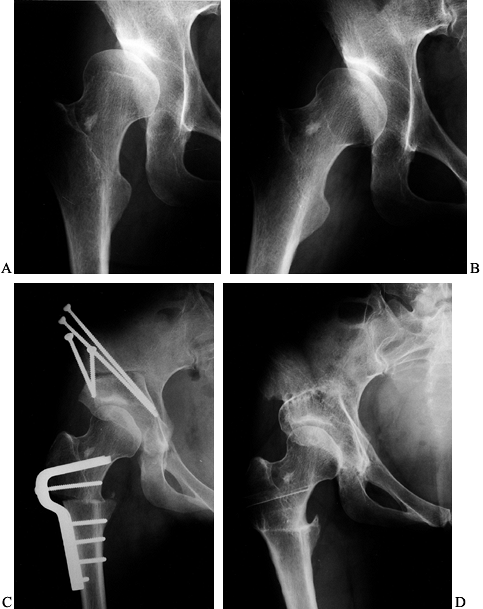

Figure 104.20. PAO for Perthes disease. A:

AP view of the left hip in a 52-year-old man with a history of bilateral Perthes disease. The contralateral hip had already been treated with a primary and revision total hip arthroplasties. B: AP view of the hip 3 months after PAO and trochanteric advancement. C: Preoperative false-profile view. D: False-profile view 6 months postoperatively. At 1 year he used a cane only rarely and was working without restrictions. His preoperative back and hip pain was relieved. |